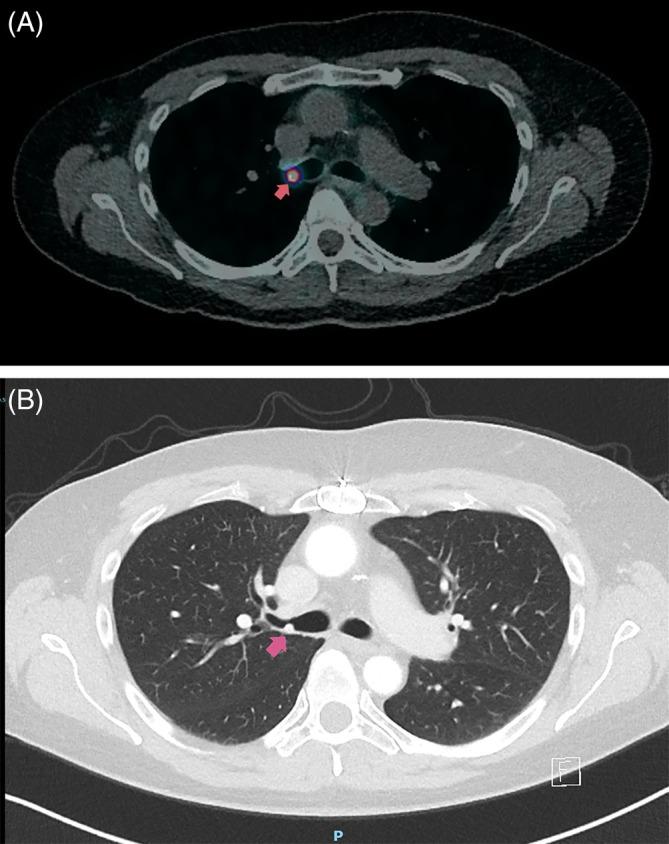

副神经节瘤是一种罕见的神经内分泌肿瘤,与嗜铬细胞瘤有着共同的胚胎学起源,但不同的是,它们位于肾上腺髓质之外。文献报道的发病率为每百万人中有2至8例。肺副神经节瘤约占其中的2%。副神经节瘤可因儿茶酚胺分泌而引起症状。其他“无功能”副神经节瘤可能会引起与占位效应或支气管内阻塞相关的症状。一旦确诊,最常见的治疗方式是肺叶切除术和支气管袖状切除术。只有少数病例报告描述了其他治疗方式,如支气管内消融。我们报告一例48岁女性患者,在琥珀酸脱氢酶B基因突变(SDHB)家族性副神经节瘤背景下,正电子发射断层扫描(PET)钇[90Y] DOTATATE扫描发现右主支气管内病变。采用氩等离子体凝固(APC)探头消融进行支气管镜治疗,以减少病变体积,症状得到显著改善,随访期间病情稳定。